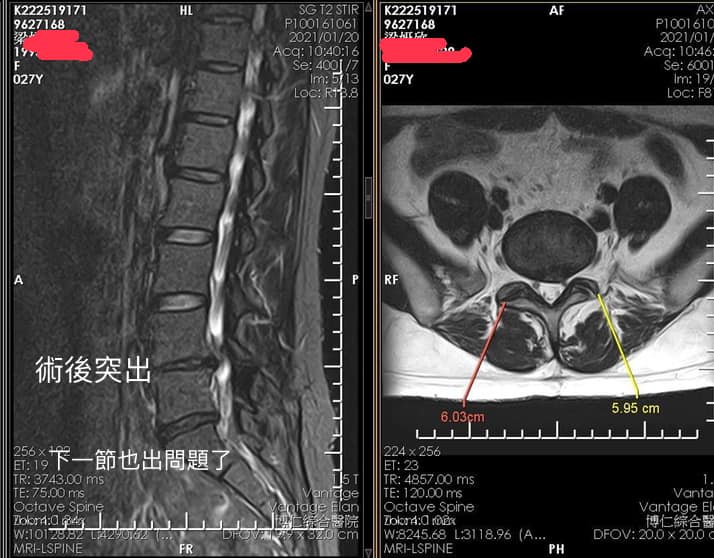

Cervical Spine Treatment Cases 腰椎治療案例 #巨大椎間盤突出一定要開刀嗎? #兩家醫學中心外科醫師說很嚴重! #有沒有辦法逆轉勝... 2021.08.10 ❖ 椎間盤突出治療醫案 ❖晨起痛爆整個人無法工作心情沮喪 😂骨科醫師說復健如果沒效可... 2022.05.12 #天才年輕賽車手巨大椎間盤突出醫案 #八周治療完全逆轉勝康復 #重新回到合法賽車場競... 2021.07.20 #腰椎滑脫痛苦不堪 #右腳麻痛無法彎腰刷牙 #感謝桃園市楊小姐熱情見證 #患者親自贈送... 2021.06.15 #巨大椎間盤突出醫案 #真的逆轉勝超感動 #三個月治療完全徹底改善 #脊刻救援成功 #徹... 2021.06.12 ⭕️L4L5巨大椎間盤突出治療醫案 🌟八週之內解除危機逆轉成功 😁順利降級成功解封印 💪... 2021.07.08 #腰椎多節椎管狹窄治療醫案 #腎臟病患者可接受中醫微創筋膜療嗎? #感謝台北市信義區張... 2021.06.01 #腰椎手術失敗綜合症候群 #感謝桃園呂伯伯熱情見證 #何時必須優先考慮再次動刀 #脊刻... 2021.07.31 #感謝新店吳先生熱情見證 #車禍後導致椎間盤突出醫案 #傳統復健六周無效痛苦不堪 #脊... 2021.05.29 #椎間盤突出治療醫案 #破紀錄三週解決 #真的逆轉勝 #感謝新莊周先生熱情見證 #脊椎整... 2021.05.26 #脊椎滑脫合併椎管狹窄醫案 #感謝台北市曹阿姨熱情見證 #之前大痛到無法走路只能拐杖... 2021.05.14 #嚴重椎管狹窄醫案導致寸步難行 #最嚴重走路無法超過十公尺 #疼痛到整個人憂鬱到不... 2021.05.07 #巨大椎間盤突出醫案逆轉勝 #感謝台北士林王先生熱情見證 #脊椎整合中醫微創療法 #原... 2021.04.29 #台灣越南國際醫療成功 #脊椎整合中醫微創療法逆轉勝 #腰椎椎間盤突出醫案 #曾經大痛... 2021.04.23 #椎間盤突出逆轉勝醫案 #原本骨科建議開刀 #脊刻救援成功 #感謝雲林患者陳小姐熱情見... 2021.04.09 ← 上一頁 7 8 9 10 11 下一頁 →